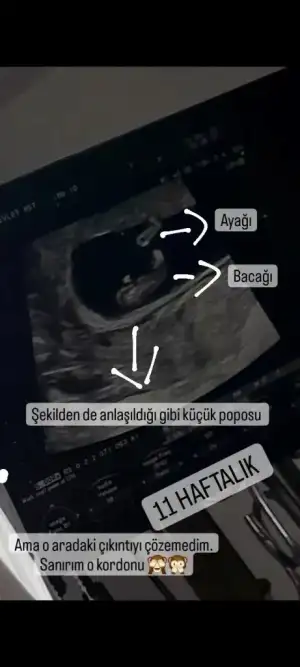

Olduğum yer merkeze uzak olduğu için hastane ve doktor tercihim az. Olsun 1 ay geçsin daha detaylı öğrenirim. Bir ara erkeğe benziyor dedi, sonra kıza da benziyor olduğu için tereddüt yaşıyoruz. Mide bulantısı hiç yaşamadım ama bu demek değil ki, bebek erkek o zaman işte göstereceği anı bekliyorum. Sadece ramzi teorisine göre erkek çıkıyor. Nub teoriside tereddütlü gözükmüyor. 11 haftada bacak arasında sadece bir çıkıntı var ama kordona da benzettim aslında ama video çektiğim için iyice baktım kordonu bir tık daha yukarıda kalıyor aslında diyorumsenin bence bebişin kız ya çünkü erkekler hemen belli ediyor kendini, nazlı olduğu için ben kız diyorum1 ay çok uzun bi

Resmimiz bu şekildeVar mı ultrason resmi eğer nub belliyse cinsiyet tahmini yapabilirim bende.

Oyyy çoook tatlı, nub göremedim sanki yani tam emin değilim ama 3 çizgi gözüküyor bu da kız bebeğe işaret. Rabbim sağlıkla nasip etsin kucağına almayı. Cinsiyeti öğrenince haberini bekliyorum. Senin içine doğan bir şey var mı? Ben hamileliğimi ilk öğrendiğimde eşimle birlikte erkek hissettik ve eşim oğlum demişti karnımı severek. Rüyada bile eşim, ben ve amcası erkek gördü bebeği ama bakalım ayrıntılı ultrasonu bekliyorum.Resmimiz bu şekilde

Çok teşekkür ederim.Oyyy çoook tatlı, nub göremedim sanki yani tam emin değilim ama 3 çizgi gözüküyor bu da kız bebeğe işaret. Rabbim sağlıkla nasip etsin kucağına almayı. Cinsiyeti öğrenince haberini bekliyorum. Senin içine doğan bir şey var mı? Ben hamileliğimi ilk öğrendiğimde eşimle birlikte erkek hissettik ve eşim oğlum demişti karnımı severek. Rüyada bile eşim, ben ve amcası erkek gördü bebeği ama bakalım ayrıntılı ultrasonu bekliyorum.

Mide bulantısı olayı tamamen uydurma. Oğlumda 2 kere serum yedim kusmaktan boğazım acıyordu. Kız sanmıştım herkes de öyle demişti. Şimdi de bulantım var ama bu sefer kusamıyorum ama hep o hisle yaşıyorum herşey kokuyorOlduğum yer merkeze uzak olduğu için hastane ve doktor tercihim az. Olsun 1 ay geçsin daha detaylı öğrenirim. Bir ara erkeğe benziyor dedi, sonra kıza da benziyor olduğu için tereddüt yaşıyoruz. Mide bulantısı hiç yaşamadım ama bu demek değil ki, bebek erkek o zaman işte göstereceği anı bekliyorum. Sadece ramzi teorisine göre erkek çıkıyor. Nub teoriside tereddütlü gözükmüyor. 11 haftada bacak arasında sadece bir çıkıntı var ama kordona da benzettim aslında ama video çektiğim için iyice baktım kordonu bir tık daha yukarıda kalıyor aslında diyorum. Ama yan çekim olduğu için kordonda olabilir. Yani kutumda çok farklı şeyler hissediyorum ben Hamdi Beyden gelecek teklifi bekliyorum

bahsettiğim resmi de bıraktım